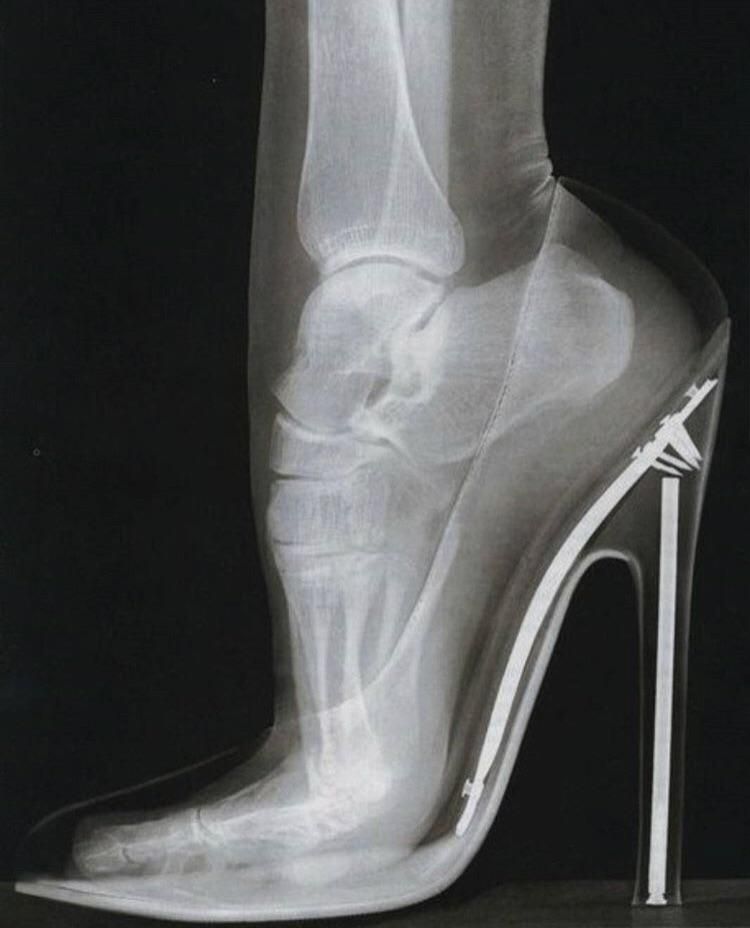

Rentgen stopy w bucie na wysokim obcasie